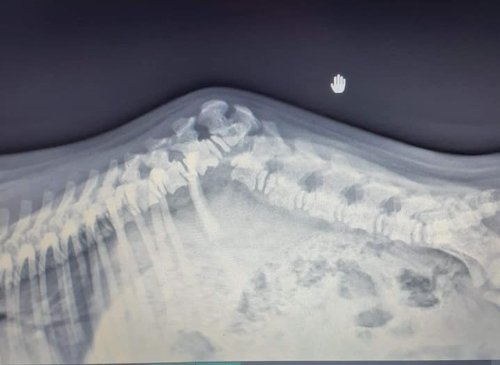

Es wurde eine neue Röntgenaufnahme gemacht. Die Wirbelsäule hat sich im Bruchbereich etwas stabilisiert, und sie hat sich verlängert, wodurch der „Huckel“ nicht mehr so auffällig ist. Moses soll so weiter trainieren wie bisher: Viel, aber nicht zu viel Bewegung, und dabei möglichst unterschiedliche Bewegungsabläufe auf verschiedenen Untergründen, um alle Muskeln und Sehnen gut aufzubauen. Sofern sich keine Komplikationen einstellen, soll er erst wieder zur Kontrolle kommen, wenn er ausgewachsen ist.

Ein Jahr ist Moses nun schon alt. Das war natürlich ein Termin zum Feiern, aber auch, um ihn wieder in der Tierklinik vorzustellen. Er wurde geröntgt, und es zeigte sich, dass der Zustand seines Rückens den Umständen entsprechend stabil ist. Von einer Operation wurde abermals abgeraten. Es ist weiterhin Muskeltraining angesagt, bei dem Moses aber nicht überanstrengt werden darf. Seine Pflegefrauchen achten sehr darauf.

Im vergangenen Jahr war Moses auch wieder zu einer Kontrolluntersuchung in der Tierklinik. Das Röntgenbild zeigte, dass die Stelle des Bruches sich verkapselt hat und somit recht stabil geworden ist. Die Ärzte sagten „Wenn man versucht, Wunder zu verbessern, geht das meistens schief.“ Daher wurde vereinbart, dass nichts unternommen wird, um die kleineren Einschränkungen, die Moses noch hat, zu beseitigen. Er soll sich wie bisher ausreichend und angepasst bewegen sowie jährlich zur Kontrolle vorgestellt werden (außer es tritt etwas Akutes auf, was einer Behandlung bedarf).